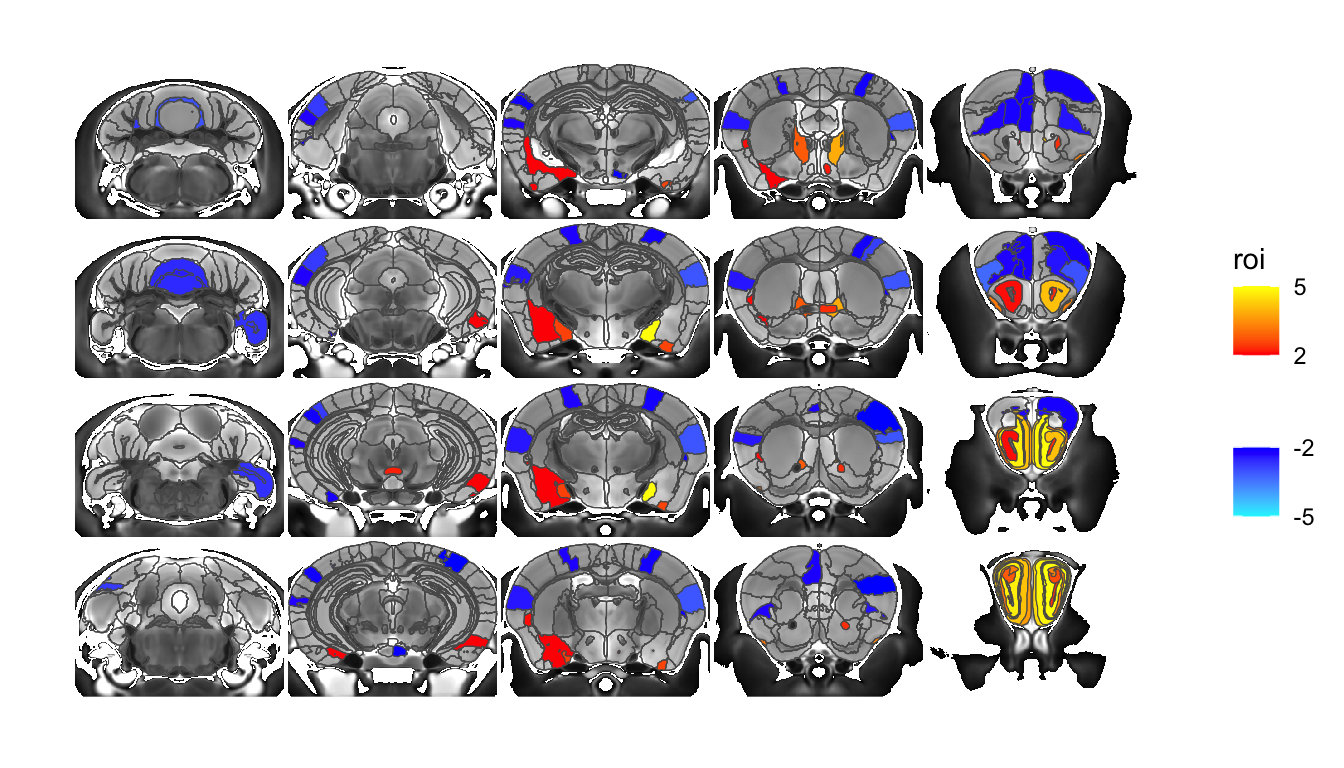

Let’s take a look - we’ll show the background anatomy, an overlay of the atlas, and the ROI based output for the gonads term.

MRIcroscope(sliceList) %>%

add_anatomy(low=500, high=1400) %>%

add_roi_outline() %>%

add_roi_overlay(data=hlm, column=tvalue.GM)You can click on this (or any image) to get a larger preview. Also note that when you run it you’ll see some warnings about coordinate systems etc. that can be safely ignored.

For one more example let’s overlay the voxel map of the same stats term instead: